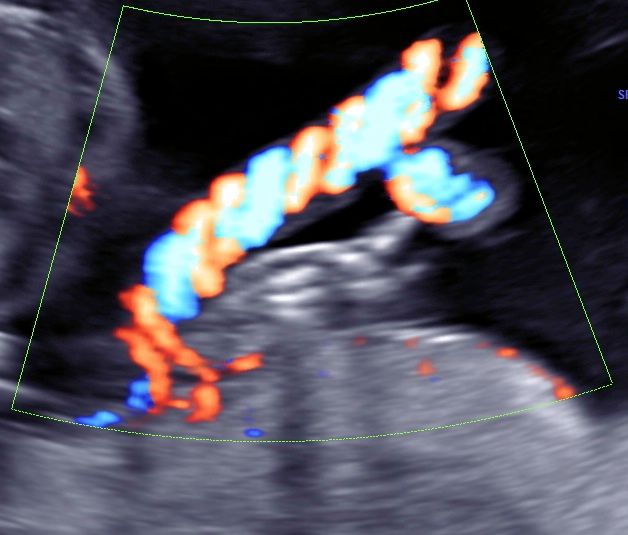

• Ecocardiografia fetale

• Ecografia morfologica